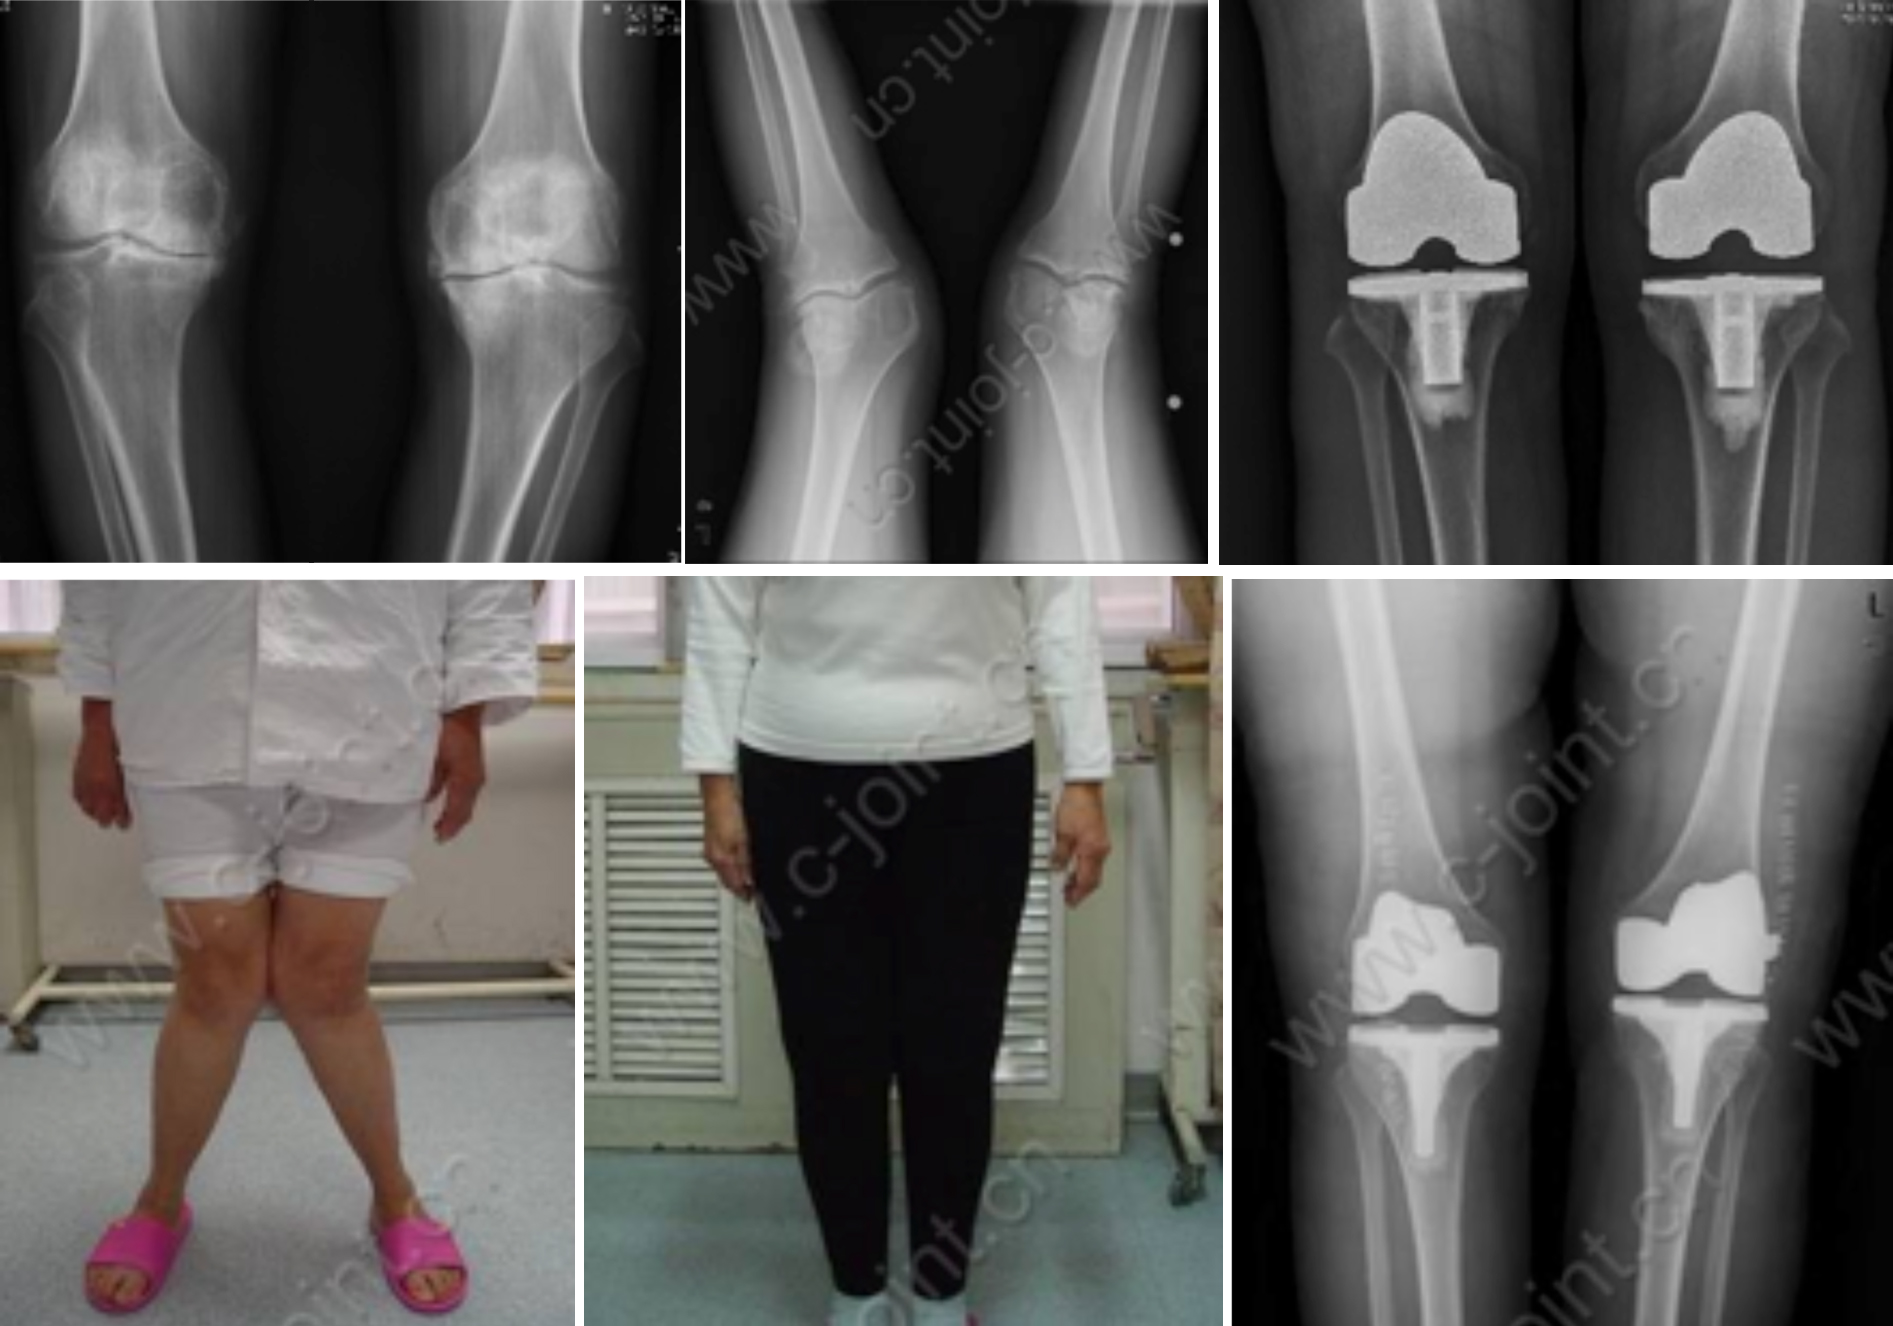

二、截骨矫形

成人肢体骨与软组织畸形、如:斜颈畸形、臀肌筋膜挛缩症、先天性骨关节疾病畸形、先天性髋关节脱位分期治疗、先天性马蹄内翻足矫形术、X型腿、O型腿、创伤后畸形、小儿麻痹后遗症的肢体畸形矫形、脑性瘫后遗症的肢体畸形矫形等。

胫骨截骨矫形手术(HTO)

股骨远端截骨矫正膝外翻